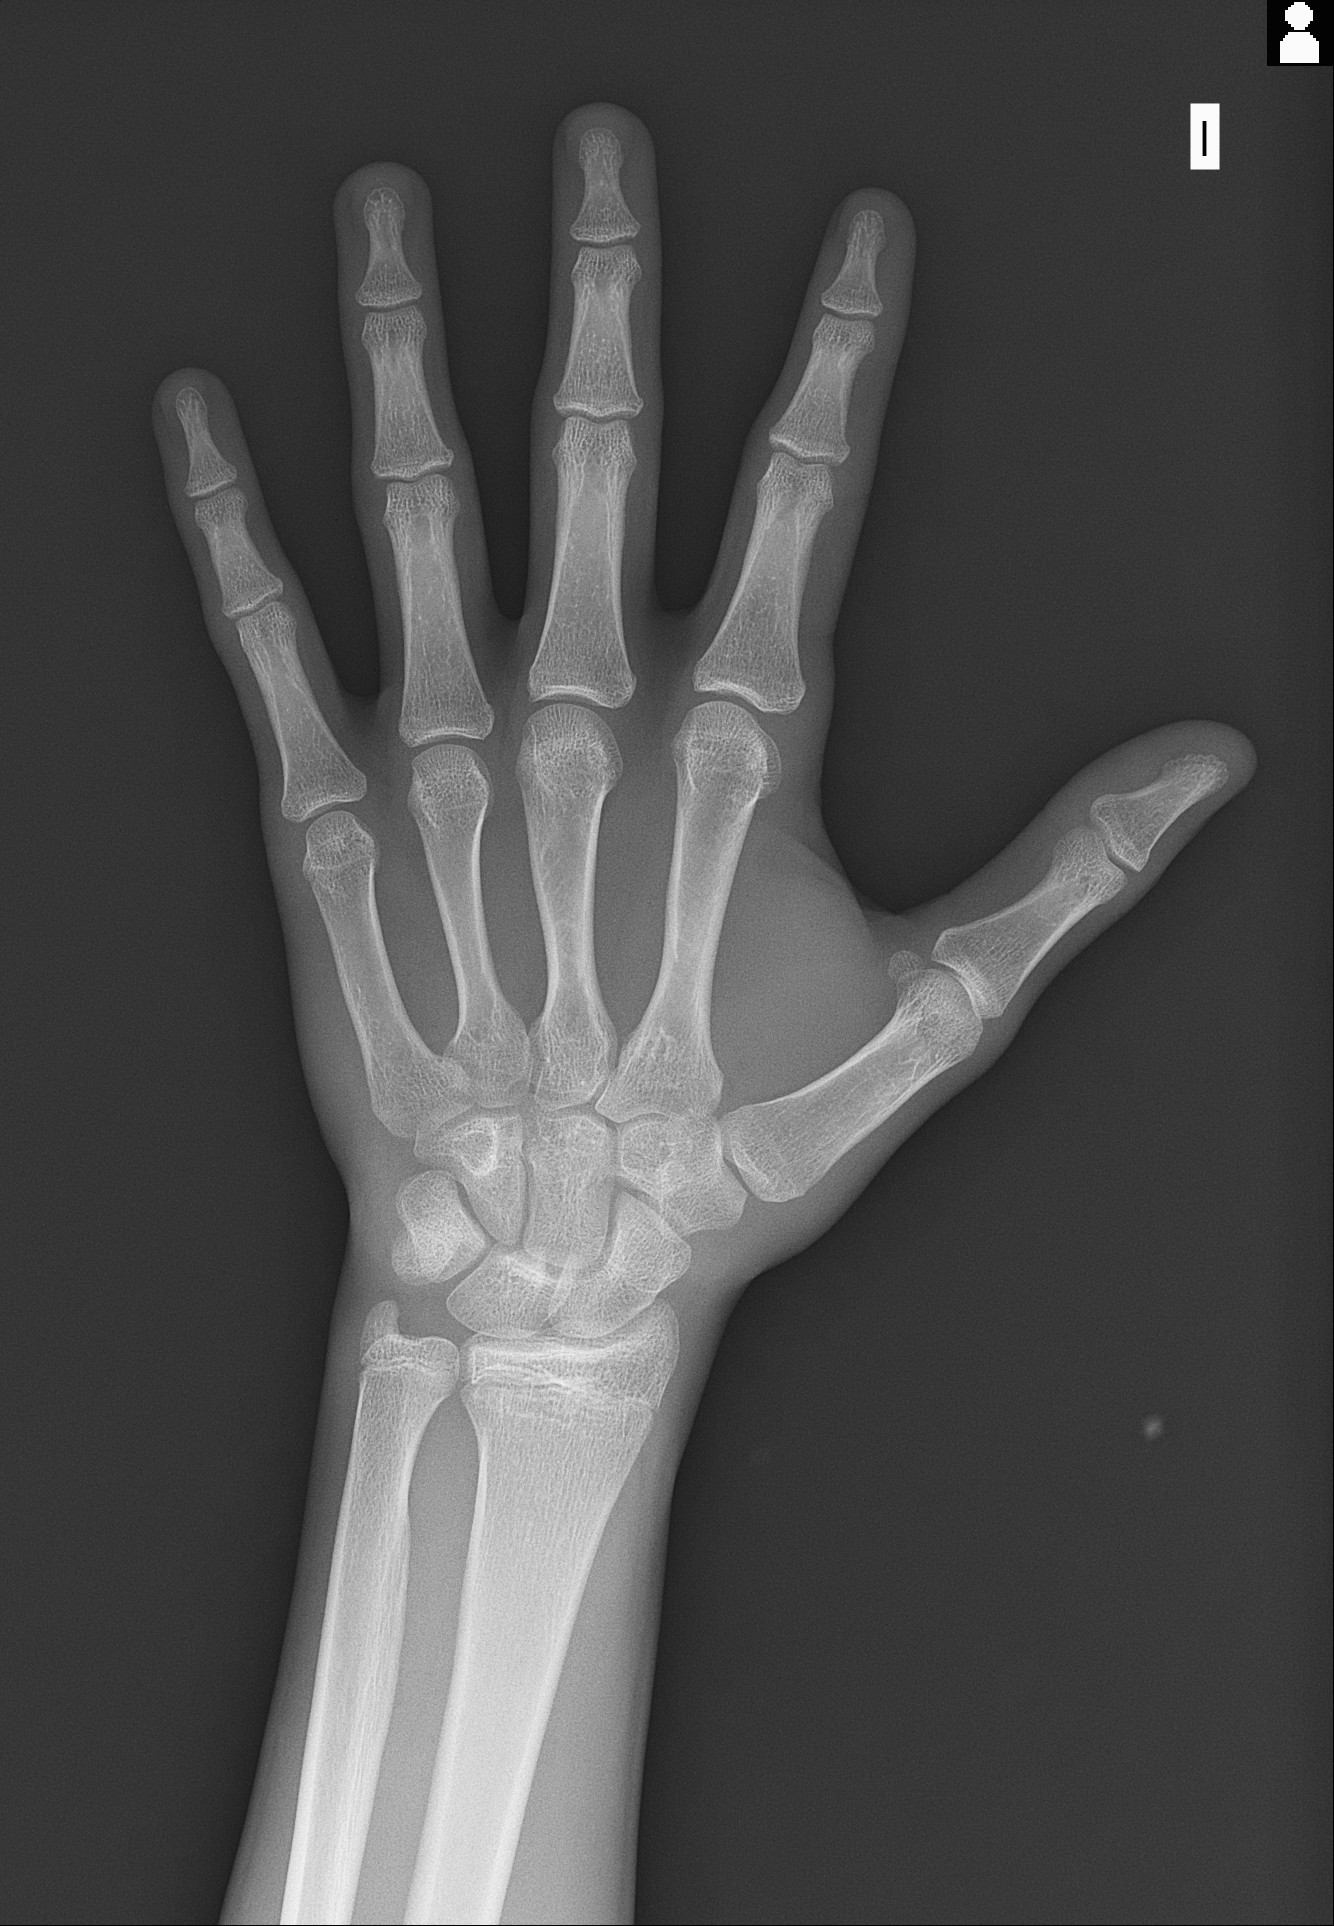

These were my growth plates 1 or 2 weeks ago. @Genio told me its over and that ai wouldnt do nothing since they r fusing this month. But im so fucking desperate. My E2 is already pretty low and under 24 pg/ml and during the day i experience knee pain and finger pain whilst typing. I wanna go lower so bad i wanna grow. HGH wont do shit for me im already 17 very soon and i donnt have the money for it and my parents know everything im getting monitorized nigga.

I beg you for an answer since my time is running out. My calculated bone age is 5 months older than me (based on my calculations)

dont make me cry :( but there are like little lines they are clearly not closed but also not open but i dont think

Still open but very late stage. If your serious then get x rays of both of your tibia and femur plates on both legs. HGH is not expensive btw

I saw your xray from 6 months ago ans it seems the wrist hasnt increased in age alot, how is ur growth velocity?

I grew 1 cm I think in the past months that’s why I thought about ai. In the past 3 months about 1 cm

Your wrist isnt fused yet from the xray. If u start high dose gh+ai u might grow 1-2cm max but it depends on your knee growth plates.